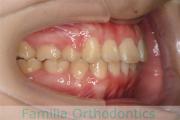

No.19V-044

- 上顎前突

- 13歳

- 女性

- 上:

- 44

- 下:

- 8558

- 主な使用装置:

- FEA

- 治療にかかった費用:

- 85万円

出っ歯を治したいということで小学生の時に来院されました。中学生になるまで経過観察をして、診断、上下左右から小臼歯を抜歯してマルチブラケット法にて治療を行いました。2年強、30回程度の通院が必要でした。

口元の突出感も大きく改善しています。

- ≫治療前

-

上下とも前歯の叢生(でこぼこ、凹凸、ガタガタ)がありましたので、保定をしっかりやらないと後戻りのリスクが出てきます。